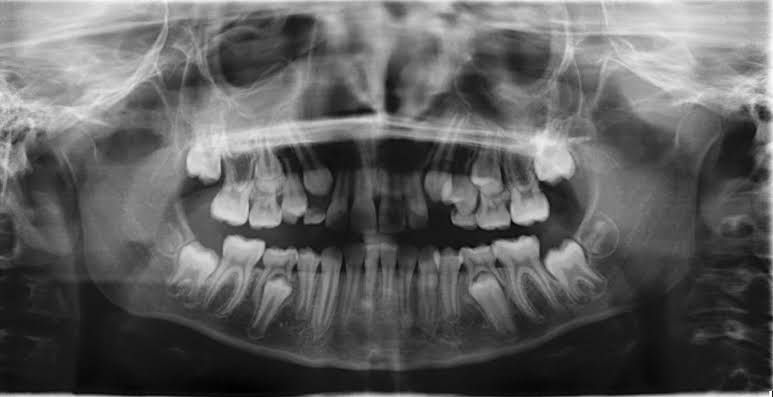

If you are having wisdom teeth removed, you may have a panoramic X-ray. This X-ray takes a picture of all of your teeth at once. It can show several things that help to guide an extraction: